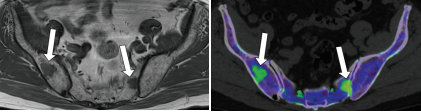

评估骨髓浸润活性

双能量硅图:硅胶假体破裂